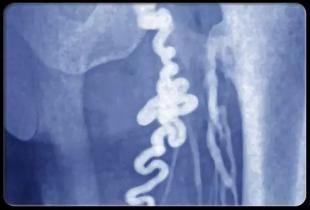

相关图片